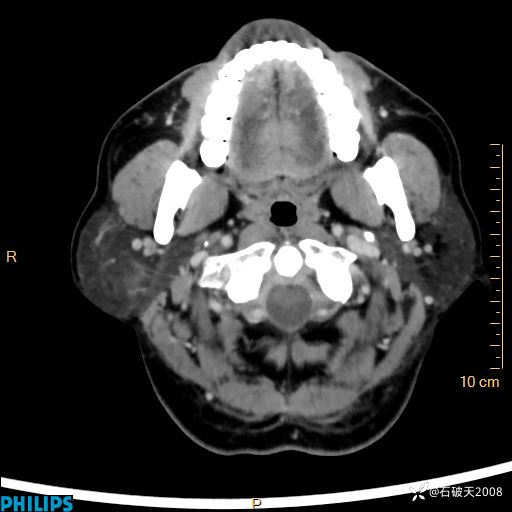

病例分享:颈部占位,一周后公布病理

男 57岁 主 诉:发现右侧颌下肿物1月余。

现病史:1月余前家属发现右侧颌下肿物。局部皮肤无红肿、热痛,无吞咽困难,无异物感,无恶心、呕吐,无头痛、头晕,无胸闷、胸痛,无发热、咳嗽、咳痰及呼吸困难。于我院行体表肿块彩超检查(2024.03.15我院)示:右侧耳下皮下软组织内低回声,未治疗。今为进一步治疗门诊以“腮腺肿瘤”为诊断收住我科,发病来患者神志清,精神可,饮食、睡眠及大小便正常,体重无明显下降。

MIP